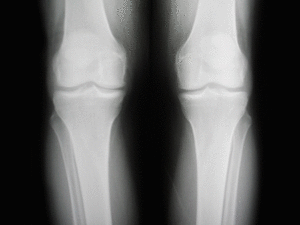

Si d’habitude ces images aux rayons X servent à déceler les fractures et autres anomalies, aujourd’hui, découvrez que la radiologie peut-être de l’art ! Et en GIFs animés SVP !